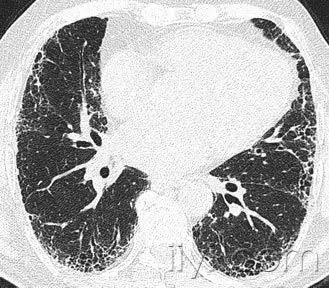

CT:正常次级肺小叶中心的点状或者线状的密度增高影,胸膜下25px范围内最明显,代表小叶内的动脉,直径约1mm。小叶中心性异常包括(1)结节(2)树芽征,提示小气道病变(3)由于临近间质的增厚或者浸润导致小叶中心结果更加清晰(4)小叶中心性肺气肿导致的异常低密度。

附图为小叶中心性肺气肿 医学百科网 | YxBaike.Com